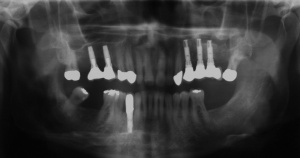

Ab dem Februar 2004 wurde der Patient zur Sicherung des Behandlungserfolges in das in der FU VIIa – Zahnmedizin seit 1996 praktizierte Recallsystem aufgenommen. Diese Erhaltungstherapie beinhaltet die bereits erwähnten Maßnahmen der Unterstützenden Parodontitistherapie (UPT). Aufgrund dienstlicher Erfordernisse (u. a. immer wieder Seefahrten des Patienten) konnte der zunächst geplante Abstand von vier Monaten nicht immer eingehalten werden. Ein Abstand von ca. sechs Monaten konnte jedoch trotz der teilweise schwierigen Rahmenbedingungen realisiert werden. Am Zahn 44 kam es im Jahr 2006 zu einem Rezidiv, sodass an diesem Zahn im September 2006 eine Lappenoperation durchgeführt wurde. Der intraoperativ vorgefundene tiefe cirkuläre vertikale Defekt führte zur Einschätzung einer langfristig fraglichen Prognose von 44. Im Zuge der weiteren Erhaltungstherapie zeigten sich bis auf 44 die parodontalen und periimplantären Gewebe völlig unauffällig: So betrugen die Sondiertiefen bei entzündungsfreien klinischen Verhältnissen durchweg zwei bis drei Millimeter. Auch radiologisch zeigten sich keine Auffälligkeiten. Es gab keine Progredienz der ehemaligen parodontalen Erkrankung, die Osseointegration der Implantate zeigte keine Veränderungen (s. Abb. 7). Erhöhte Sondiertiefen verblieben lediglich am Zahn 44. Nachdem sich trotz regelmäßiger Nachsorge an 44 keine Entzündungsfreiheit der marginalen Gingiva erzielen ließ und die Zahnlockerung von 44 zunehmend stärker wurde, erfolgte im Jahre 2010 die Entfernung des Zahnes und der Ersatz durch eine implantatgetragene Krone (s. Abb. 8). Die Erhaltungstherapie wurde fortgeführt, Behandlungsmaßnahmen über die Inhalte der UPT hinaus waren bis zur Entlassung des Soldaten im Jahre 2012 nicht erforderlich. Der Patient blieb jedoch auch nach der Entlassung aus dem aktiven Dienst Patient des Hauses, sodass die Erhaltungstherapie in der FU VIIa – Zahnmedizin fortgeführt werden konnte. Im April 2013 stellte sich der Patient mit Beschwerden am Zahn 45 vor, der Zahn wies zudem eine Lockerung des Grades II auf. Die durchgeführte Röntgendiagnostik (s. Abb. 9) zeigte eine Wurzelfraktur im apikalen Wurzeldrittel, ein Zahnerhalt von 45 war nicht möglich und der Zahn wurde noch in gleicher Sitzung entfernt. Zur Versorgung der Lücke wären verschiedene prothetische Lösungen möglich gewesen. Letztlich fiel die Entscheidung zugunsten eine Extensionsbrücke von regio 45 auf 48. So konnte die Implantatkrone 44 belassen und mit dem Lückenschluss mittels einer vergleichsweise einfachen und schnellen prothetischen Versorgung auch die Schaltlücke 46 geschlossen werden. Der Patient befindet sich nach wie vor in der FU VIIa in der Erhaltungstherapie, die Fotos zeigen den aktuellen klinischen Befund in der Aufsicht des Ober- und Unterkiefers (s. Abb. 10, 11).

Mit der Transplantation eines freien Schleimhauttransplantats im Januar 2001 konnte die aktive parodontologische Therapie abgeschlossen werden, der Patient wurde zur Unterstützenden Parodontitistherapie in das Recallsystem der FU VIIa aufgenommen. Der Patient stellte sich dabei halbjährlich zur Durchführung von professionellen Zahnreinigungen vor, die durch die bereits beschriebenen Elemente der Erhaltungstherapie ergänzt wurden. Ein wichtiges Element der Erhaltungstherapie ist die regelmäßige parodontale Diagnostik mit der Erstellung eines Parodontalstatus, um gegebenenfalls Rezidive frühzeitig erkennen und behandeln zu können. Im Jahre 2006 kam es an einzelnen Zähnen zu Rezidiven, es konnten Sondiertiefen von bis zu 7mm sondiert werden. Es wurde daher ein Scaling/Rootplaning der rezidivierenden Taschen durchgeführt, an einzelnen Zähnen erfolgten im Jahre 2008 zudem weiterführende parodontalchirurgische Maßnahmen im Sinne von Lappenoperationen (s. Abb. 16). Im Rahmen der unterstützenden Parodontitistherapie erfolgte neben den schon erwähnten halbjährlichen professionellen Zahnreinigungen im November 2012 eine erneute subgingivale Instrumentierung an 21, 24, 28, 41, 46. Die letzte Vorstellung des Patienten erfolgte im April 2015 (s. Abb. 17, 18, 19). Dabei stellte sich die marginale Gingiva entzündungsfrei dar, die approximalen Sondiertiefen betrugen durchschnittlich zwei bis drei Millimeter, geringgradig erhöhte Sondiertiefen verbleiben an 21, 28, 36, 47. Die häusliche Mundhygiene des Patienten stellte sich wie schon über den gesamten Beobachtungszeitraum mit einem API von 30 % als gut dar. Die periimplantären Gewebe zeigten sich bei der Vorstellung im April 2015 unauffällig.